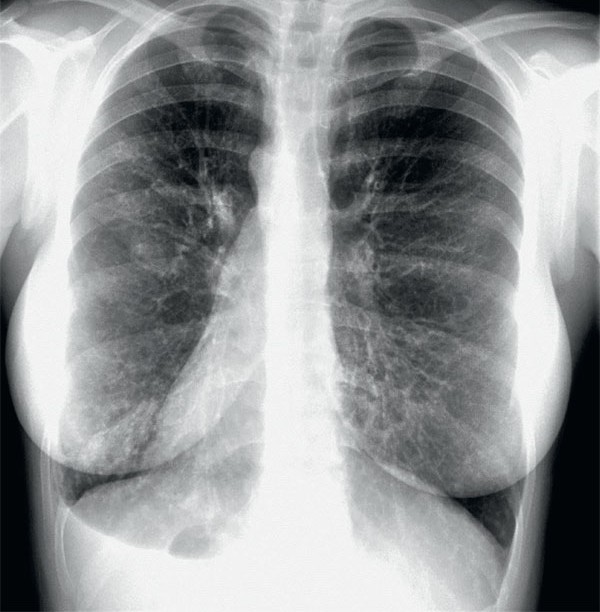

>warming up the snatch>get to 60kg >feel sharp pain in my upper back >power through it for the rest of the day>second day I can barely move>get xrayed and see thisIs it fucking over for me? I’m an Olympic hopeful for 2028

>>77050843Look at my c6. It’s not supposed to look like that

>>77050849that's your T6. your C6 is not present in this image. it could be spondylolisthesis, no one here knows doe

>>77050849C is cervical, and I see fuckall at your D6. nice tits tho. Also that's a very underexposed xray

Bro an x ray won't show a slipped disc or anything because it's soft tissue damageGet an MRI then get back to us Also nice tits

Is this what you're tripping over? Idk, it dosent look good, maybe a slipped disc.Your only hope now is get a real strong back to compensate.Didn't the doctor have any feedback for you, or did you just want to show us your tits, you slut? Not that i'm complaining.

>>77052406spondylolisthesis get a MRI